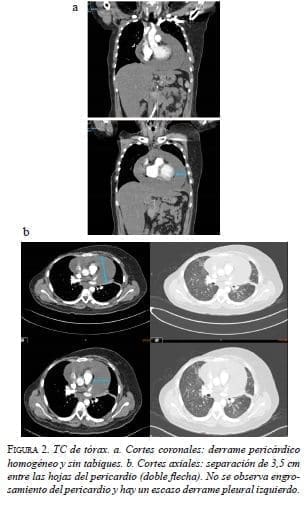

En la tomografía de tórax (TC), se observó un derrame pericárdico con separación de 3,5 cm entre las hojas del pericardio y un derrame pleural izquierdo (figura 2).

Se realizó una ventana pericárdica más pericardiectomía e instalación de un catéter pleuro-pericárdico subcutáneo (tunnelized) mediante toracoscopia izquierda. El líquido pericárdico era de color cetrino. No se identificó carcinomatosis pleural o pericárdica. El examen citológico del líquido pericárdico fue negativo para neoplasia maligna y en la histopatología de las biopsias de pericardio y de pleura parietal se observó un mesotelio reactivo, negativo paraneoplasia maligna (figura 3).